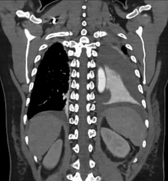

患者因外伤来诊时,CT检查提示骨盆骨折伴盆腔血肿,同时意外发现Stanford B型主动脉夹层——这是两个都可能危及生命的急症。面对如此复杂情况,介入科团队第一时间行动。

在患者生命体征尚平稳但潜在风险极高的情况下,我们结合CT增强检查及三维重建结果,考虑盆腔存在活动性出血,果断通过绿色通道经股动脉穿刺行盆腔动脉造影,竟发现至少3条动脉存在损伤情况。随即迅速以导丝导管结合技术超选择插管至出血责任动脉并成功实施栓塞术。相对传统开腹探查手术,这项微创介入技术不仅大大节省了宝贵的抢救时间,更是避免了开腹手术的创伤,用最小的代价稳定了患者的生命体征,为后续治疗赢得了宝贵时间。

患者盆腔出血病情稳定一周后,经严格控制血压、稳定心率、卧床制动等治疗后,复查主动脉CTA提示主动脉夹层较前有所进展。主动脉疾病MDT团队——包括心血管外科、介入医学科、麻醉科、重症医学科(因患者合并骨盆骨折、血尿,还邀请了肾内科、泌尿外科、四肢关节骨科)等多学科专家进行了深入讨论,考虑该患者Stanford B型主动脉夹层累及范围广泛,如同体内“不定时炸弹”,具有限期手术干预指征,需要及时精确拆除。

△注:主动脉内膜呈螺旋形撕裂,夹层形成,随时可能因主动脉破裂、脏器缺血坏死等而危及生命。